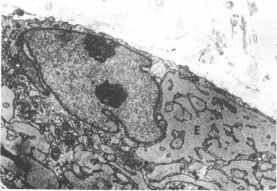

Figure 6 Electron micrograph of the intracellular structures of an activated fibroblast. Note the two nuclei and markedly dilated rough endoplasmic reticulum surrounding the nucleus. (Reproduced from the British Journal of Ophthalmology, Risco et al [1] with permission from BMJ Publishing Group Ltd.)

Electron Microscopy: As with examination under light microscopy, examination under electron microscopy also reveals epithelial hyperplasia and acanthosis, disrupted basal layer, and thickened stroma with irregularly oriented collagen fibrils (Figure 5).[9][1][22][23] Macrophage-like cells can be found in the stroma.[1] In addition to the above, electron microscopy allows visualization of intracellular structures of the activated fibroblasts, including: fibrillar cytoplasm, irregular nuclei with compact chromatin, abundant cytoplasm with prominent rough endoplasmic reticulum, and increased amounts of mitochondria, glycogen, and granules (Figure 6).[9][18][1][22] Again, findings on ultrastructural studies can differ based on stage of keloid, and in the later stages, activated fibroblasts are rarer.